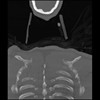

23 ANGIO,CE,Cor-MIP,5.000,ANGIO,Cor-MIP,